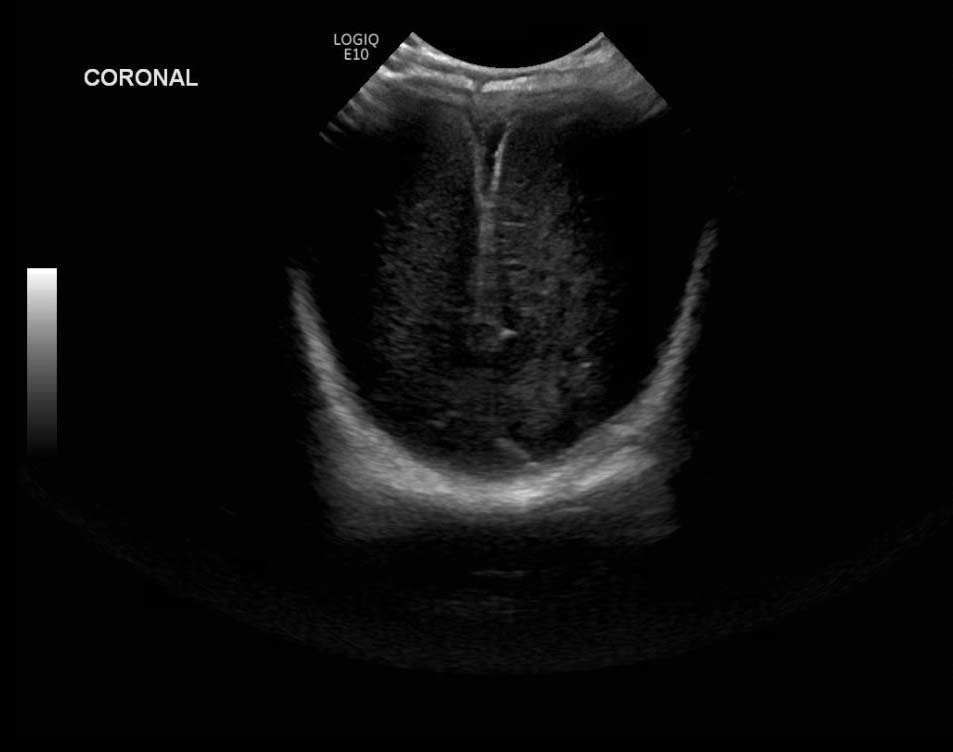

Age: 4 days (born at 24 weeks)

Sex: Male

Indication: Evaluate for germinal matrix hemorrhage

Grade 2 germinal matrix hemorrhage

Sample ReportLeft germinal matrix hemorrhage involving the caudothalamic groove and layering in the occipital horn of the left lateral ventricle without hydrocephalus (grade 2).

No abnormal brain parenchymal echogenicity or extra-axial collections.

Premature sulcation pattern.